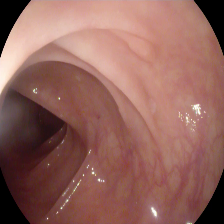

To show the effectiveness of our decoder consistency training approach, we compared our model with and without our consistency training approach. Table 2 shows the results of our model’s performance with and without consistency training. Using our consistency training approach, we are able to reduce false positive rates and improve the segmentation results for Kvasir-SEG [7], ClinicDB [1], ETIS [10], and EndoScene [13] datasets. Sample segmentation results as seen in Figure 2 also support these improvements.

imageRefer to caption

GTRefer to caption

U-NetRefer to caption

UNet++Refer to caption

SFARefer to caption

PraNetRefer to caption

MSNetRefer to caption

SANetRefer to caption

Plu nCRefer to caption

Plu wCRefer to caption

Figure 2: Sample segmentation results of the benchmark models compared with PlutoNet without (Plu nC) and with consistency training (Plu wC). Images shown in the first column belong to Kvasir, ClinicDB, ColonDB, EndoScene, and Etis datasets.